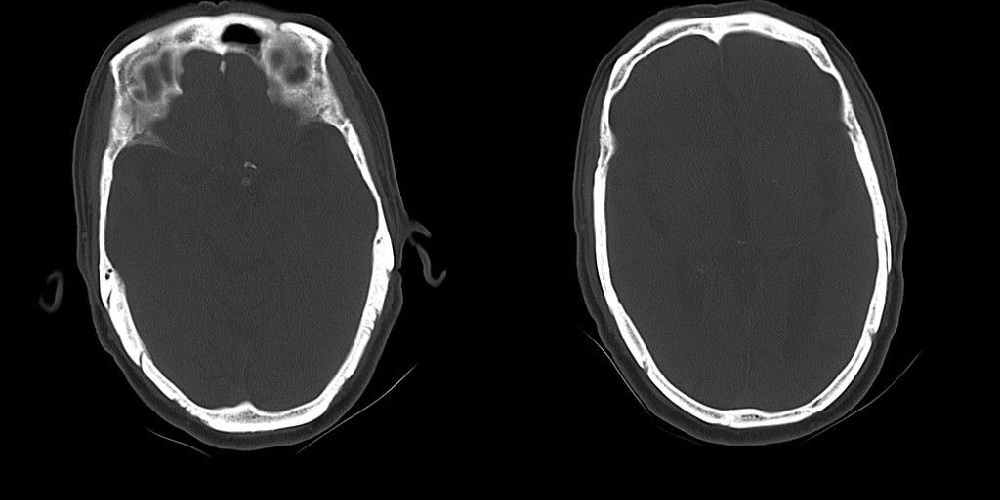

标题: CT25311:箭头所指是问题么?

该患者因头疼来诊,发现枕骨不规则缺损。

蛛网膜颗粒压迹,讨论过很多了,年龄大了不考虑lch;脑白质疏松。

箭头所指:蛛网膜颗粒压迹。

蛛网膜颗粒压迹。脑萎缩。